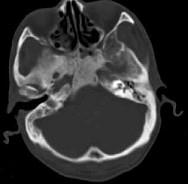

男性,56岁,鼻咽癌放疗后复查,CT扫描如图所示,请选择正确的答案()A.化脓性骨髓炎B.骨结核C.致密性骨炎D.放疗后骨炎E.骨瘤

问题 男性,56岁,鼻咽癌放疗后复查,CT扫描如图所示,请选择正确的答案()

选项 A.化脓性骨髓炎 B.骨结核 C.致密性骨炎 D.放疗后骨炎 E.骨瘤

答案 D